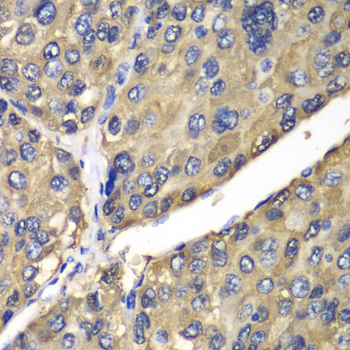

Immunohistochemistry of paraffin-embedded human liver cancer using CES1 antibody at dilution of 1:100 (400x lens).